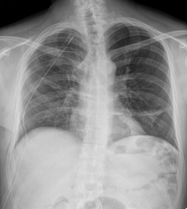

![]() |

RĂ©gression du pneumothorax droit./Drain en place au niveau apical droit./OpacitĂ© en bande linĂ©aire au niveau du tiers infĂ©rieure de lâhĂ©michamp pulmonaire gauche./Scissurite droite./Silhouette cardiaque dâaspect normal./Absence dâanomalie du gril costal./ | StabilitĂ© du pneumothorax droit./Drain apical droit en place et fonctionnel./Bande opacifiante au niveau du tiers moyen de lâhĂ©michamp pulmonaire gauche./LĂ©gĂšre scissurite droite./ | Diminution du Pneumothorax gauche./Drain thoracique positionnĂ© Ă l'apex gauche./OpacitĂ© linĂ©aire sur le tiers supĂ©rieur de l'hĂ©michamp pulmonaire droit./ | RĂ©gression marquĂ©e du pneumothorax droit./Disposition dâun drain au niveau apical gauche./OpacitĂ© linĂ©aire dans le tiers infĂ©rieur de lâhĂ©michamp pulmonaire gauche./NormalitĂ© du gril costal et des parties molles./ |